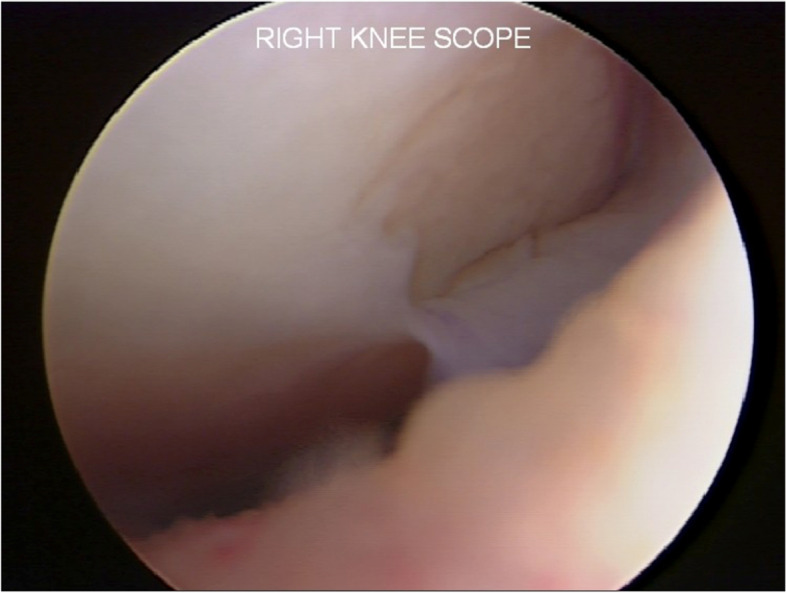

Fig. 10.

Second-look arthroscopy revealed a healed patellar lesion and fibrillations of the patella (Grade II according to ICRS classification). 324 × 149 mm.2 (144 × 144 DPI)